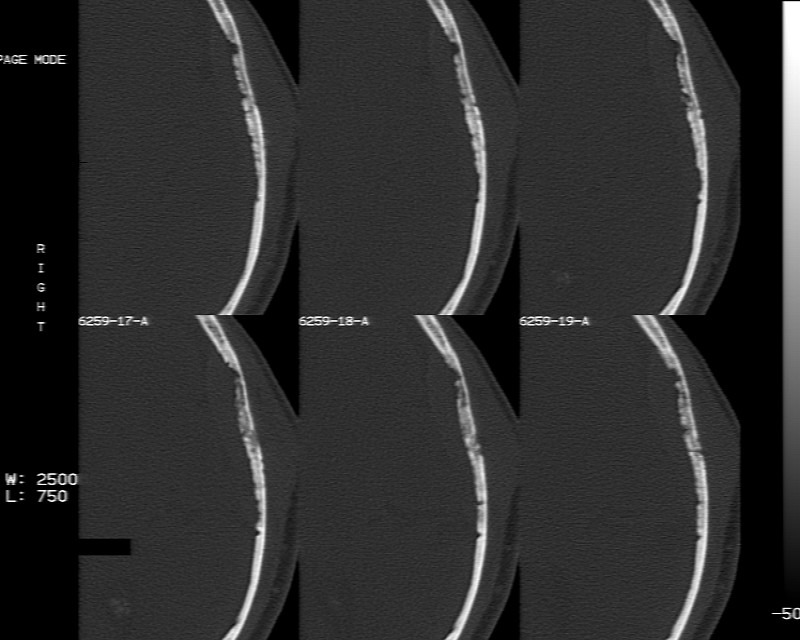

m70y, 2个月前发现左颞部有'包'隆起,近来自觉增大,无外伤无任何不适症状而就医,触诊包块质地较硬无移动无波动无皮温升高,胸片示右上肺陈旧结核....,ct扫描见左颞骨翼板局部内外骨板骨质破坏,似筛孔状,外板侧有骨膜线状增生,伴局部软组织丘状肿块,内板下梭形肿胀硬膜增厚翘起......颅内脑无异常.考虑骨良性病变 1.低度骨感染.   2.嗜酸性肉芽肿. 3.不排外骨结核...建议其穿刺活检,但患者失踪,追踪到结果定将公告.请大家分析.

左颞骨内板不光滑,密度减低,内板下可见新月形的软织密度影。脑实质轻度受压,外板外见膨胀形稍高密度影。考虑嗜酸性肉芽肿。建议增强扫描

骨质密度不均,骨质两旁均有软组织影,考虑嗜酸性肉芽肿可能性大,同时也不能除外转移瘤。